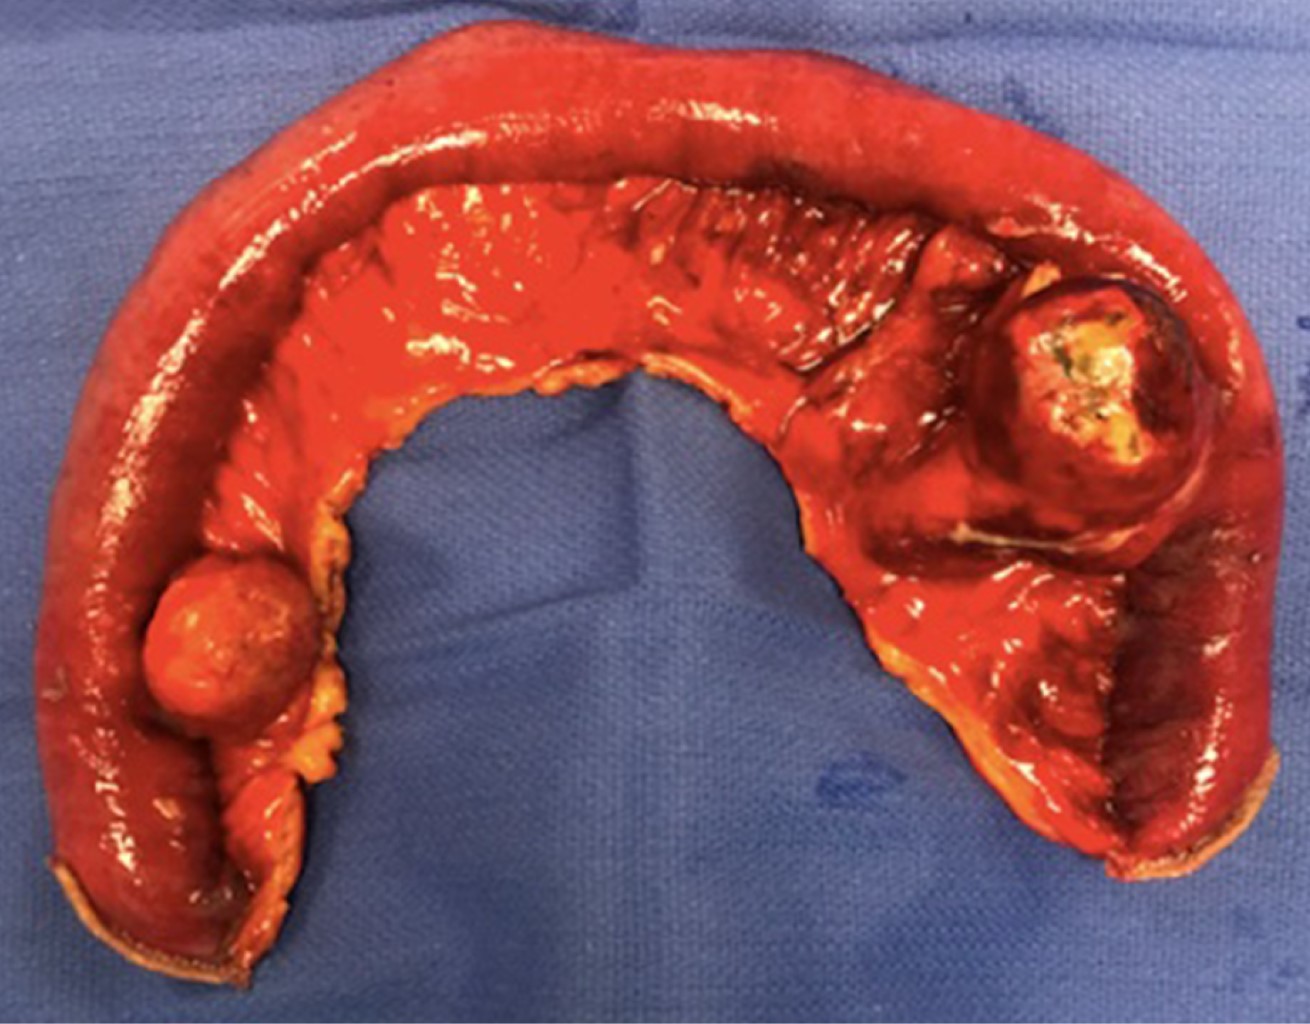

Paciente masculino de 80 años con mal estado general, dolor abdominal de 48 horas de evolución, fiebre, leucocitosis e irritación peritoneal localizada hacia la fosa iliaca izquierda. Antecedentes de dolor abdominal crónico y diarrea atribuidos a síndrome de intestino irritable y diverticulosis sigmoidea. Diagnosticado inicialmente con un cuadro de probable enfermedad diverticular complicada del colon, por lo cual se le solicitó tomografía abdominal contrastada. En dicho estudio, se reportó la presencia de un plastrón inflamatorio asociado a un segmento de intestino delgado en la zona del hipogastrio y líquido libre en la cavidad abdominal. En el segmento intestinal afectado, se observó engrosamiento parietal difuso con estriación del tejido graso del mesenterio y una imagen redondeada de 3.7 cm de diámetro con líquido y aire en su interior dependiente del asa intestinal (Figura 1A). Además, se describieron múltiples imágenes saculares, con contraste en su interior, a nivel de duodeno, íleon, yeyuno (Figura 1B) y colon.

El paciente fue sometido a exploración laparoscópica, donde se corroboró la presencia de múltiples divertículos en intestino delgado (Figura 2A), uno de ellos con franca necrosis en su pared y un absceso sellado adjunto (Figura 2B). Se realizó la resección de un segmento intestinal de aproximadamente 40 cm, que incluía el divertículo perforado y otro cercano, debido a inflamación contigua (Figura 3). El tránsito intestinal se restituyó con anastomosis mano-asistida y se realizó lavado y drenaje de la cavidad abdominal. El reporte de patología corroboró la presencia de un divertículo de 5 cm de diámetro, perforado con necrosis extensa en su pared (Figura 4). El paciente tuvo una evolución sin complicaciones.

Cuando existen múltiples divertículos, como en nuestro paciente, se recomienda limitar la resección intestinal al sitio del divertículo afectado para evitar el síndrome de intestino corto.9 En este caso, se decidió resecar un segmento de aproximadamente 40 cm donde se encontraba el divertículo perforado, pero incluyendo también otro divertículo cercano que mostraba datos de inflamación menor, pero que hubiera quedado en la cercanía proximal de la anastomosis; todo esto favoreció la pronta y adecuada evolución del paciente. El reporte de patología confirmó la presencia de un divertículo perforado con necrosis transmural.

Figura 3